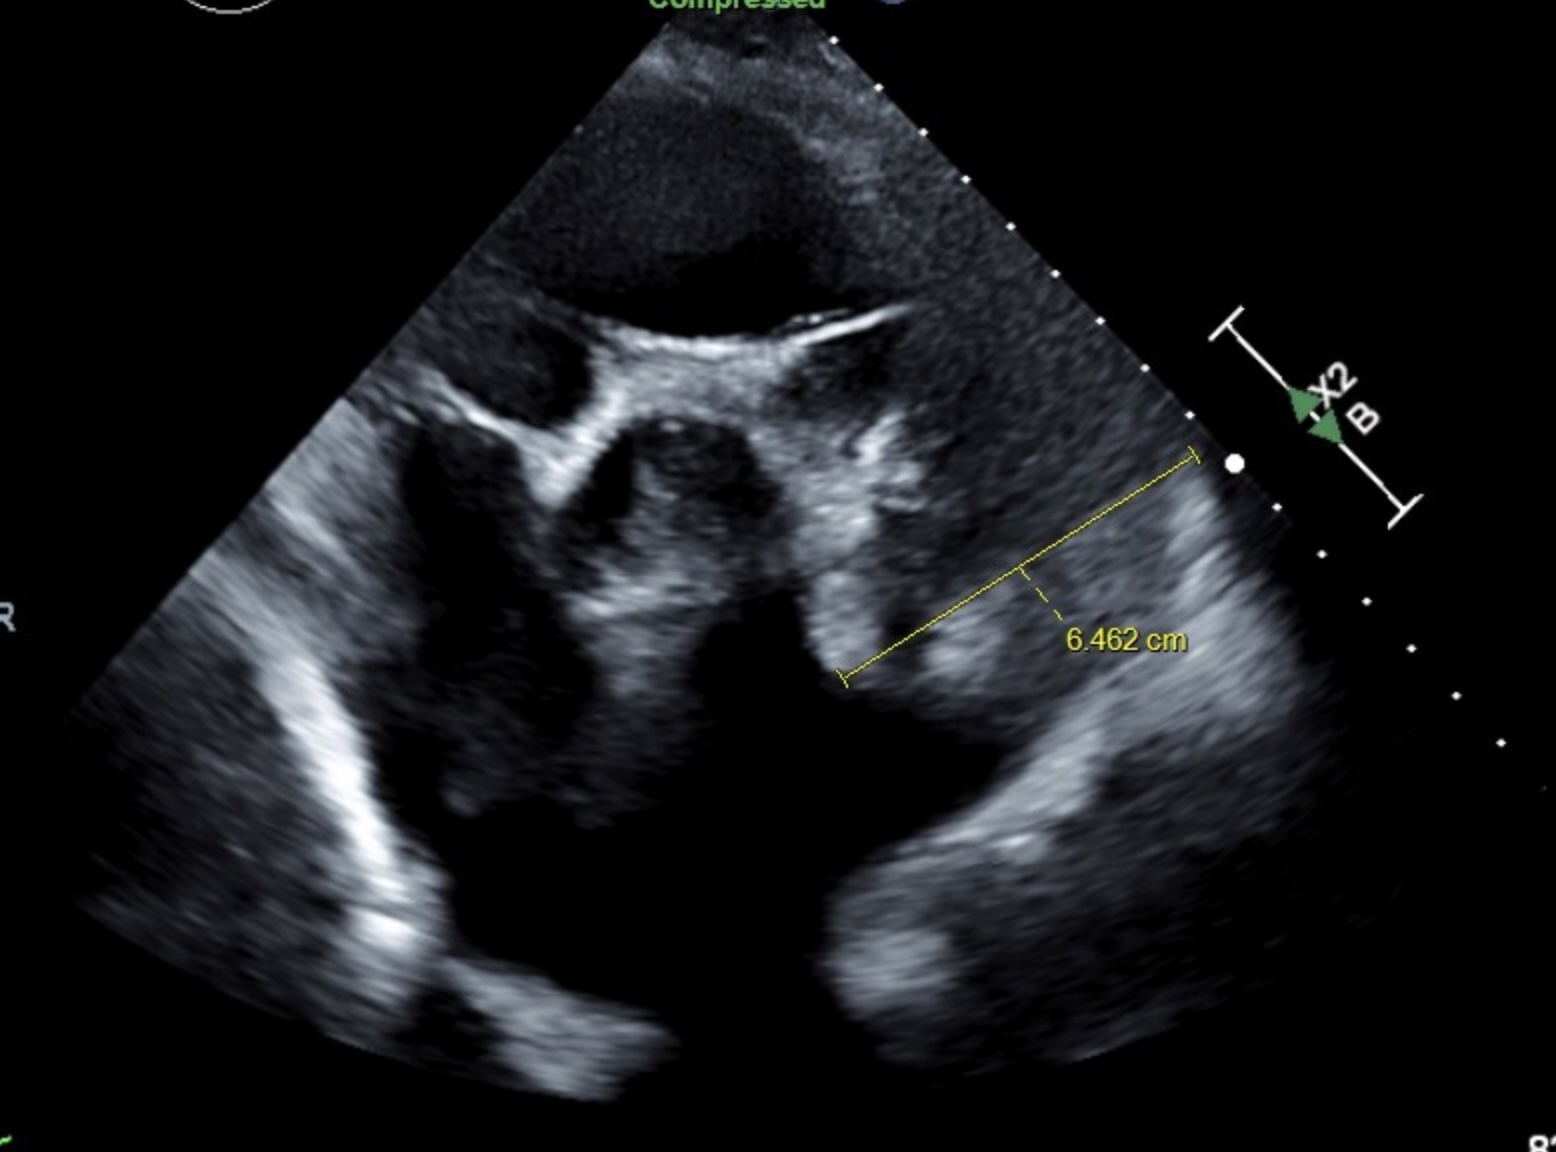

75-year-old woman with a PMH of hypertension, Group I pulmonary artery hypertension, HFpEF, non-obstructive CAD, aortic insufficiency s/p mechanical aortic valve replacement on warfarin since 02/2014, hyperlipidemia who was admitted due to altered mental status. Physical exam was remarkable for 4/6 diastolic murmur, 3/6 aortic murmur, prominent P2, and parasternal lift and no JVD or lower extremity edema. CXR incidentally showed enlarged pulmonary artery and CT chest showed PAA at 6.6 cm. Echocardiogram confirmed moderate to severe pulmonary hypertension and a markedly dilated PAA with pulmonary valvular insufficiency. In addition, she had an ascending aortic aneurysm with moderate aortic insufficiency. The two coinciding aneurysms could be distinct in etiology due to sequela of high pressure vessel wall degradation from pulmonary artery hypertension and systemic hypertension or related due to vasculitis or cystic medial necrosis/connective tissue disease. Due to multiple concomitant aneurysms, the patient is pending further workup.

Aneurysms are focal dilations with PAA larger than 29 mm and ascending aortic aneurysm larger than 44 mm. Common etiologies include vasculitis, connective tissue disease, and high vessel pressure. Due to the risk of fatal pulmonary hemorrhage, PAAs are critical. Diagnosis of PAA is via CTA and of aortic aneurysm is via TTE with annual monitoring. Surgical intervention is greater than 45-55 mm depending on risk factors for ascending aortic aneurysm and greater than 55 mm for PAA. Surgical interventions for PAAs include stent graft, aneurysmorrhaphy, lobectomy, aneurysmectomy, and pneumonectomy. Surgical resection comes with high risk in patients with severe pulmonary hypertension. Treating the underlying pulmonary artery hypertension is crucial to long term management along with determination and treatment of underlying cause.